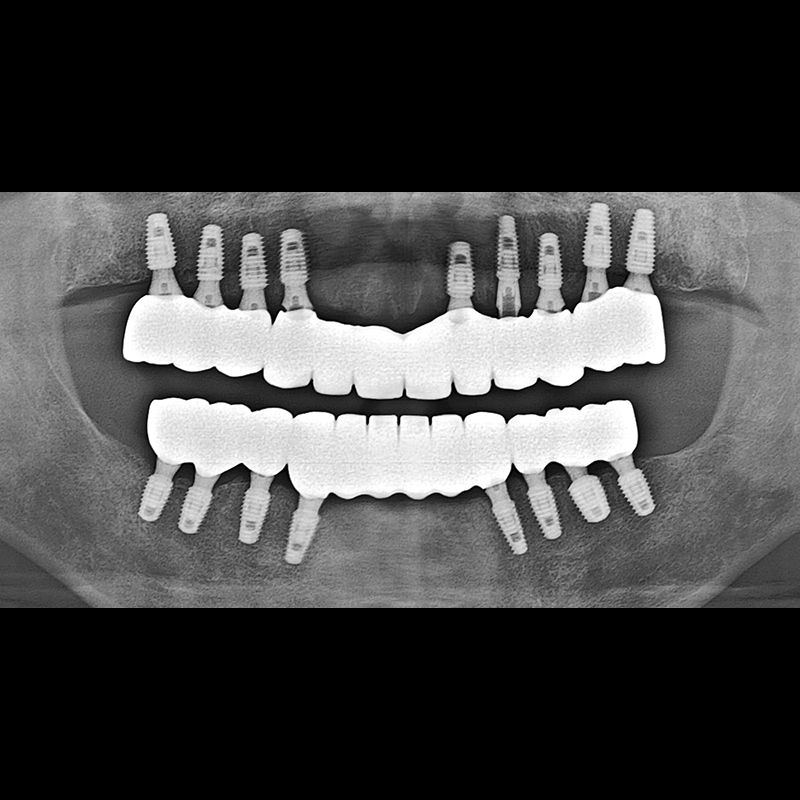

BEFORE AFTER

임플란트 전후사진 2025.05.30

결손된 치아 부분과 살리기 힘든 치아 위치에 임플란트를 식립하였습니다.